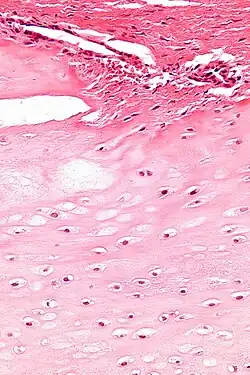

| Enchondromas are present in Maffucci syndrome | |

Maffucci syndrome is a very rare disorder in which multiple benign tumors of cartilage develop within the bones (such tumors are known as enchondromas).[1] The tumors most commonly appear in the bones of the hands, feet, and limbs, causing bone deformities and short limbs.[1]

The enchondromas affect the extremities and their distribution is asymmetrical. The most common sites of enchondromas are the metacarpal bones and phalanges of the hands. The feet are less commonly affected.[4] Disfigurations of the extremities are a result. Pathological fractures can arise in affected metaphyses and diaphyses of the long bones and are common (26%).